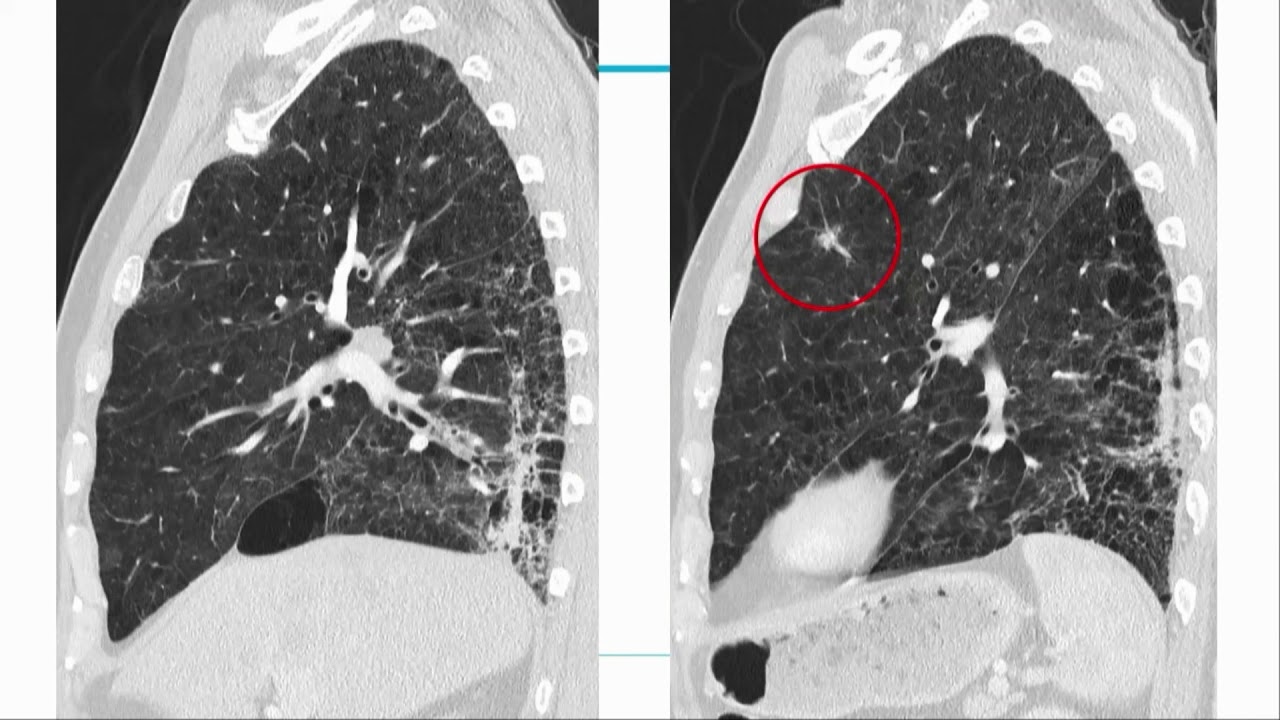

What are the latest advancements in new technologies in CT and how is artificial intelligence supporting the clinical practice? Presented by Professor Matthias Prokop, MD, PhD, of the Radboudumc University Hospital, at one of the biggest radiology departments in Europe, learn about how CT technology is evolving thanks to the implementation of AI to better support clinical decision making for improved patient care.